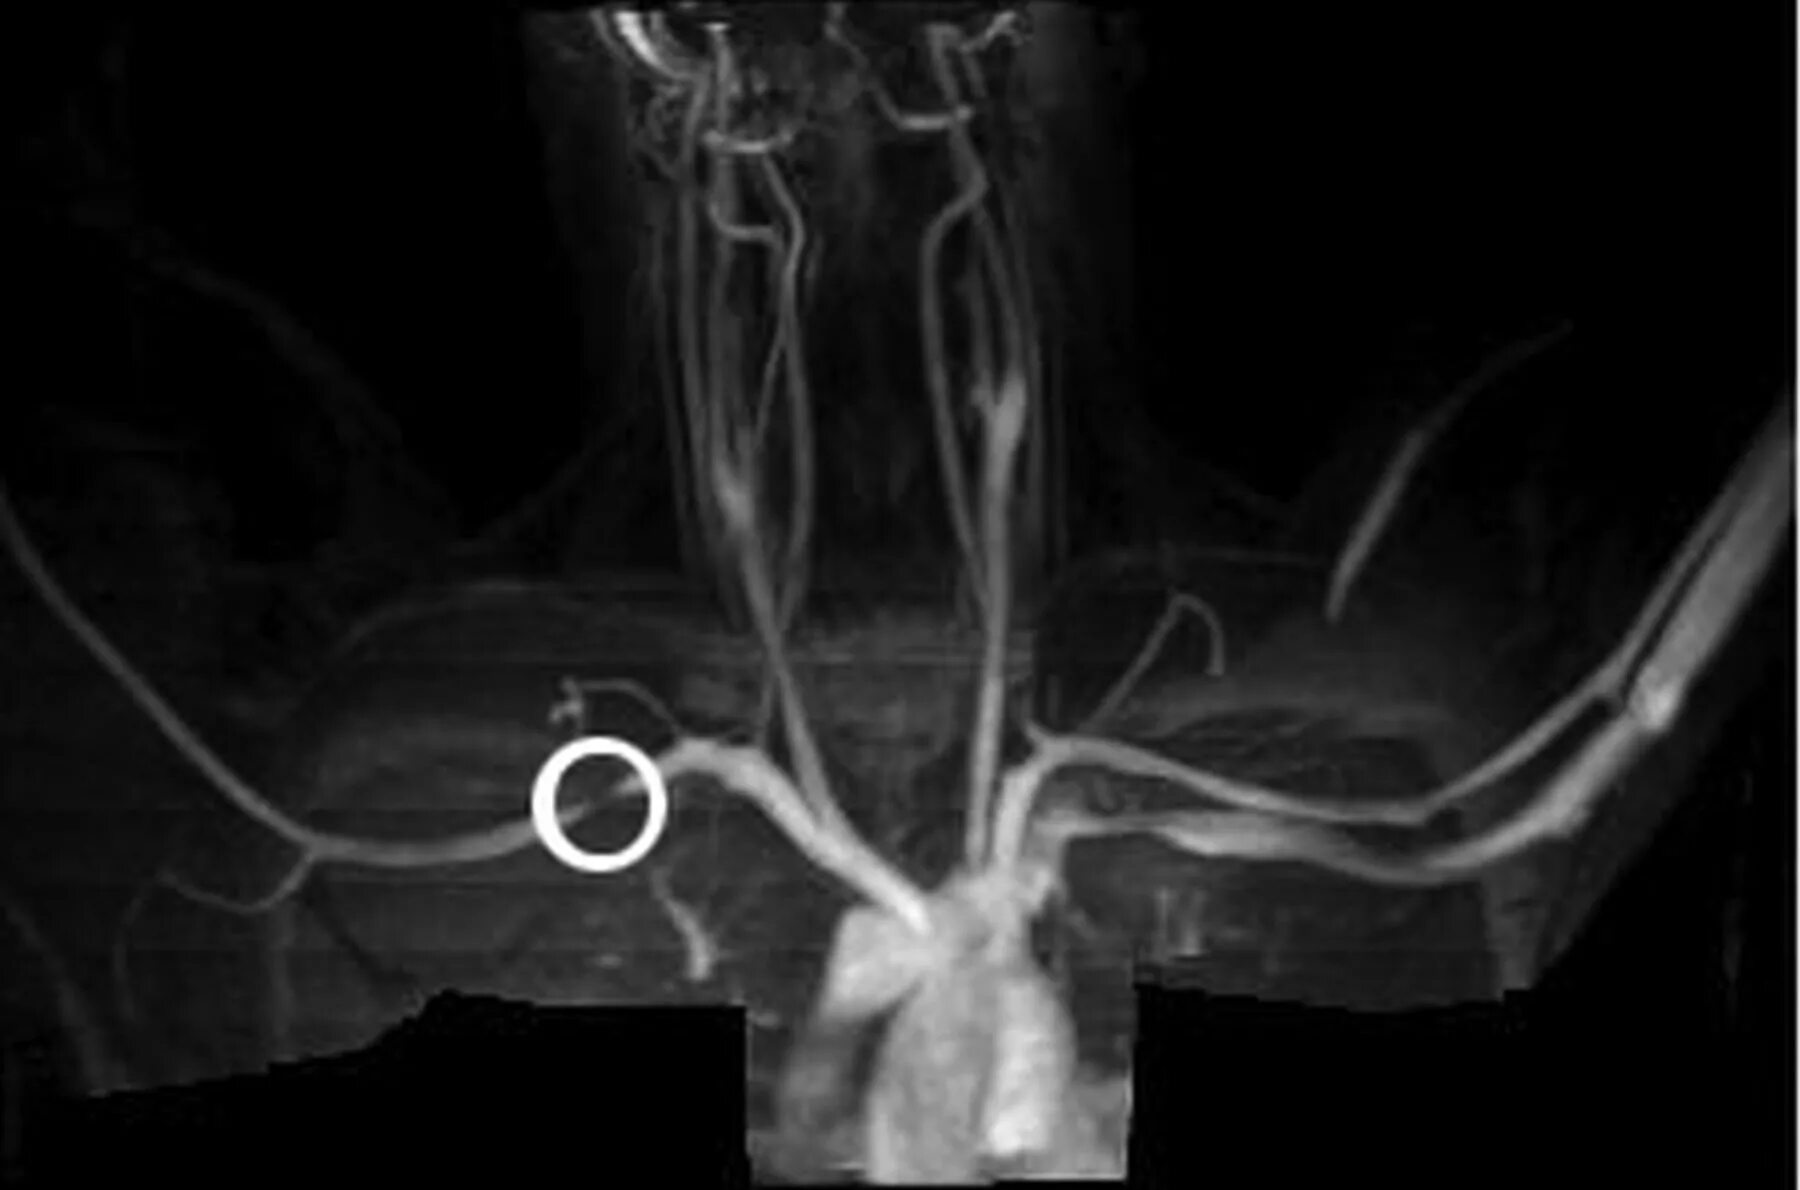

Ct search